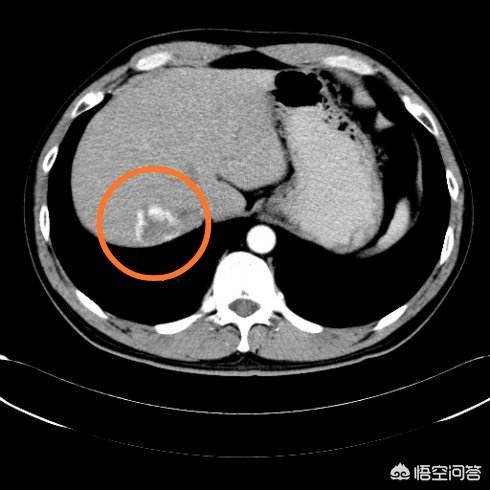

Un hémangiome hépatique n'est pas la même chose qu'un kyste du foie. Un kyste hépatique est un sac d'eau, tandis qu'un hémangiome, comme son nom l'indique, est une mare de sang, remplie de sang et non d'eau. L'hémangiome hépatique présente des caractéristiques typiques sur le rehaussement du scanner, 95% des lésions peuvent être diagnostiquées par le rehaussement du scanner ou de la résonance magnétique, l'hémangiome doit être rehaussé pour confirmer le diagnostic.

Il n'existe aucun moyen de diagnostiquer les hémangiomes hépatiques à l'aide d'un simple scanner, car les hémangiomes hépatiques et les carcinomes hépatocellulaires ont la même morphologie sur le scanner, et ce n'est qu'avec le renforcement que la différence entre les deux peut être mise en évidence.

Ci-dessous, le plus grand hémangiome hépatique que j'ai jamais vu, 16 cm de large, une femme de 54 ans, consultée pour des douleurs épigastriques.

Les hémangiomes de grande taille sont ceux qui mesurent plus de 5 cm et dont les symptômes présentent une compression importante, comme une douleur dans la région du foie, une fonction hépatique anormale et des hémangiomes situés au bord du foie. Les patientes comme celle ci-dessus, qui présentent des symptômes et mesurent 16 cm, doivent être traitées activement.